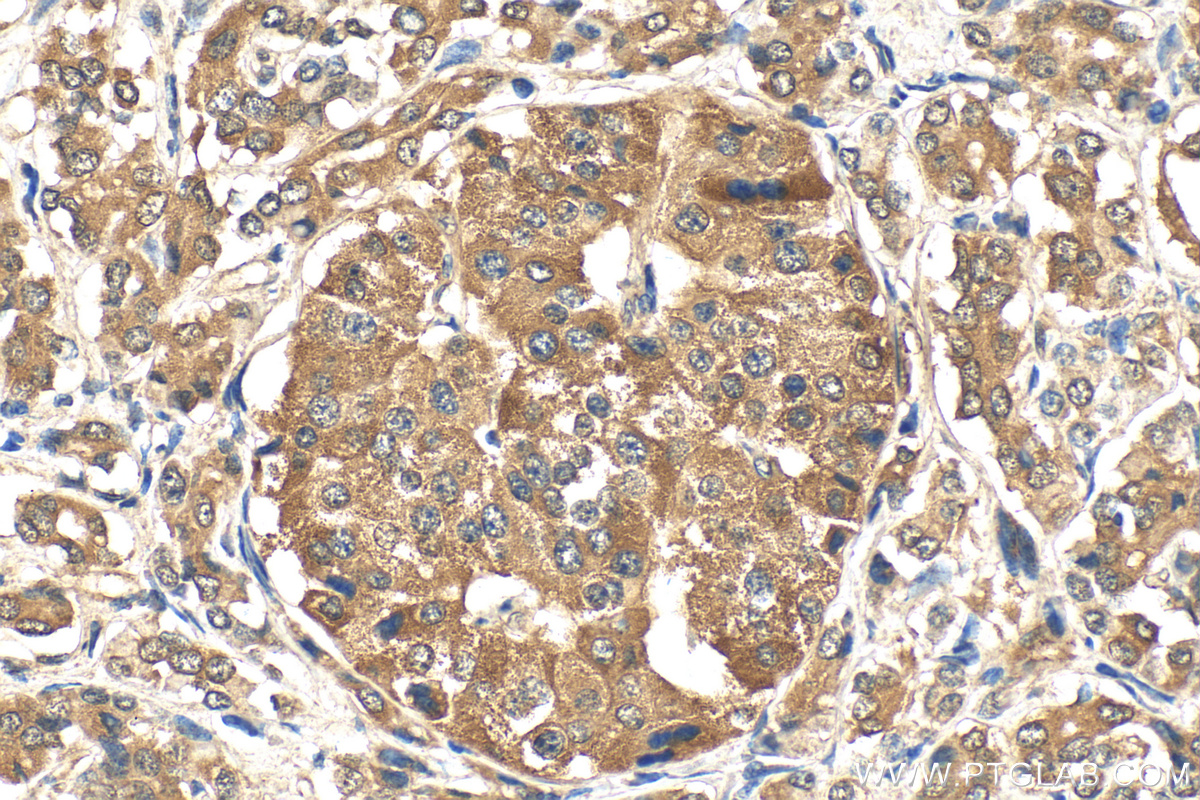

| Positive IHC detected in | human pancreas cancer tissue, human breast cancer tissue, human colon cancer tissue, human kidney tissue, human liver cancer tissue, human renal cell carcinoma tissue Note: suggested antigen retrieval with TE buffer pH 9.0; (*) Alternatively, antigen retrieval may be performed with citrate buffer pH 6.0 |

16396-1-AP targets NRF2/NFE2L2 in WB, IHC, IF/ICC, IP, CoIP, chIP, RIP, ELISA applications and shows reactivity with human samples.